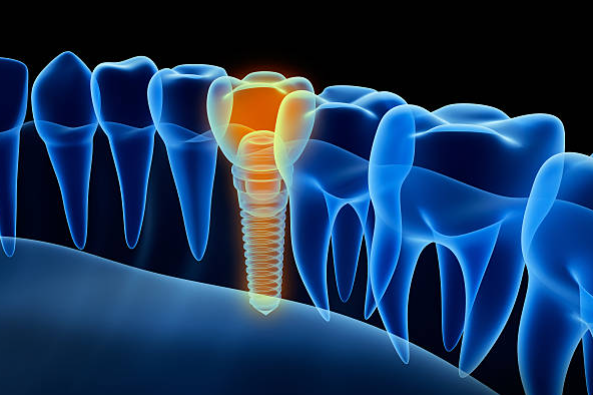

3. 2차 시술

인공치근이 잇몸뼈에 잘 자리 잡은 후, 덮어진 잇몸을 다시 열어 인공치근을 밖으로 노출시킵니다. 이때 진행하는 시술을 인공치근과 지대주를 연결하는 2차 시술이라 합니다. 지대주는 인공치근과 치아머리 크라운을 연결하는 기둥 역할을 하며, 2차 시술 후 잇몸이 완치되는데 약 1~2주 정도 걸립니다.